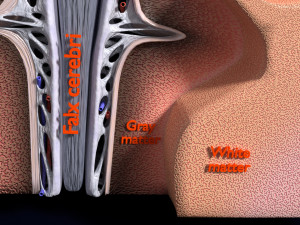

A blend model of brain along with its covering layers (meninges), skull bone and scalp labelled in detail and anatomically precise. The parts depicted are white, gray, pia, arachnoid, dura, bone, skin, fat, aponeurosis, periosteum, falx cerebri and more.